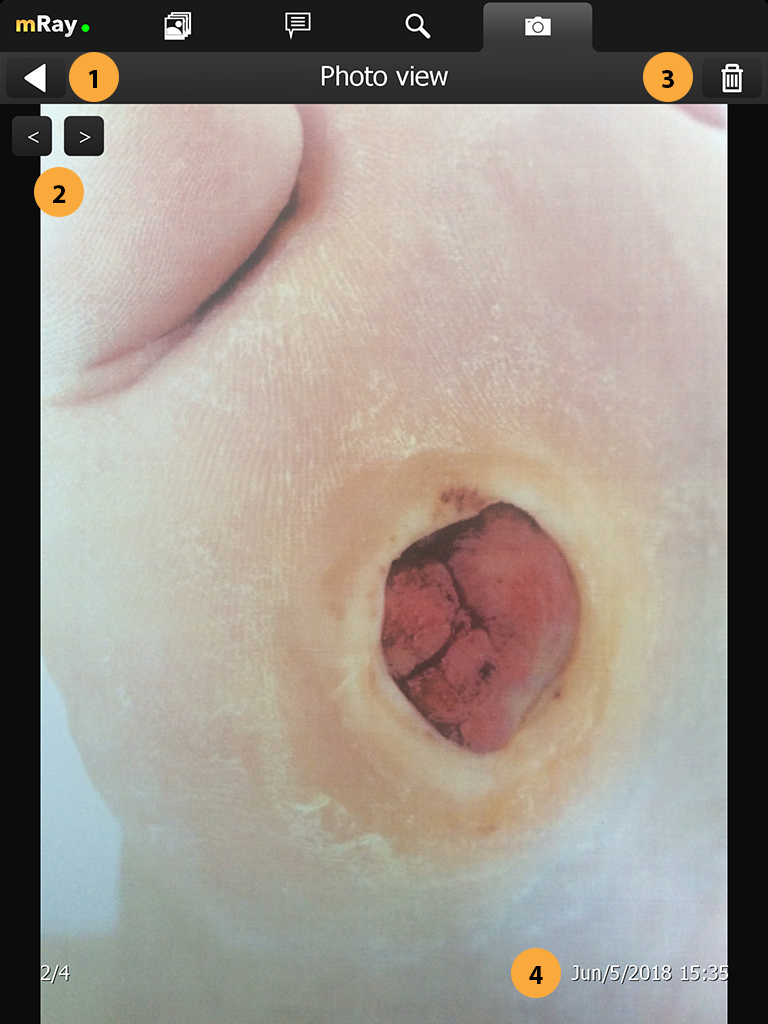

Neue Merkmale über Fotodokumentation Kamera hinzugefügt.

Aufnahme von Bildern zur Wunddokumentation. Versand der Aufnahme als DICOM Datei an ein PACS inkl. aller notwendigen Meta-Informationen